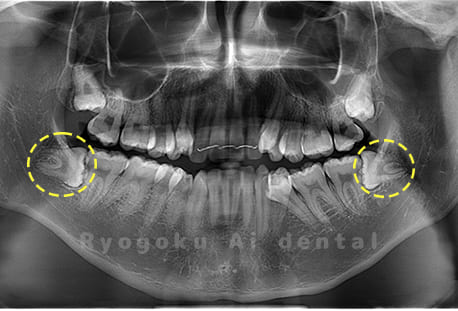

Case04

- 原因

- 上顎の親知らず、下顎の水平埋伏の親知らず

- 治療内容

- 上顎の親知らず、下顎の水平埋伏の親知らずを抜歯したケースです。

<リスク・副作用>

手術後は痛み、腫れ、痺れなどの副作用が生じる場合があります。